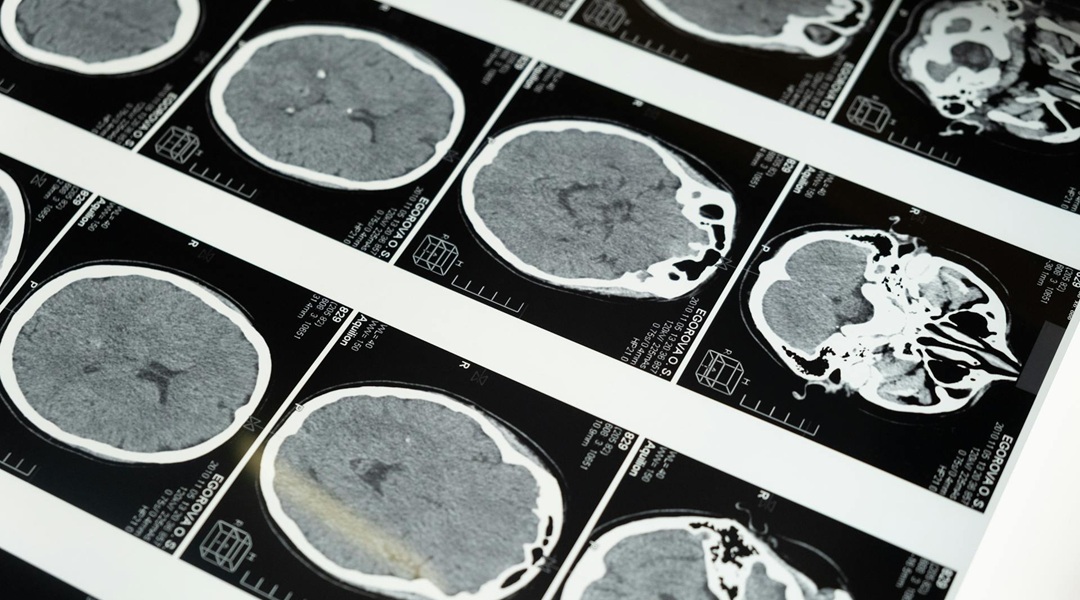

For the study, the researchers used a neuroimaging technique called fractional anisotropy. It is used to analyze the maturation and integrity of the brain’s white matter. In general, fractional anisotropy changes rapidly from birth, with the greatest jumps during the first three years, plateauing around five years of age. While not as massive, another spike occurs during adolescence, continuing into a person’s 20s.

The researchers found a definite pattern: as the methyl tags on the genes became less abundant, evidence of brain development and cognitive improvements grew. These genes are critical for insulation of axons, called myelination, speeding up and refining communication across the brain. Specifically, these developments occurred in four brain networks, including the corpus callosum, a structure that bridges the two hemispheres, as well as the posterior thalamic radiation, critical for conducting sensory and motor information. Other areas like the tapetum and white matter tracts in the cuneus and superior lateral occipital cortices also matured, as measured by changes in fractional anisotropy. Maturation in these areas brings better efficiency and with it, stronger executive function and working memory.

Notably, the researchers found that changes in fractional anisotropy, a marker of brain maturation, were the mediating factor between changes in methylation and cognitive development. Decreases in methylation at DNA segments in several genes were linked to increases in fractional anisotropy. Moreover, elevated fractional anisotropy measures in the corpus callosum and posterior thalamic radiation were directly linked to both better cognition and lower methylation in genes responsible for myelination and axonal signaling.